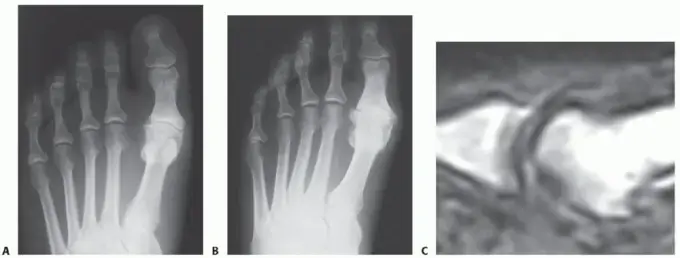

4. تكوين النتوءات العظمية (Bone Spurs):

• في المراحل المتقدمة من الفُصال العظمي، يبدأ الجسم في محاولة إصلاح التلف عن طريق تكوين نتوءات عظمية صغيرة (تسمى أيضاً العظم الزائد أو الشوك العظمي) حول حواف المفصل.

• يمكن أن تشعر بهذه النتوءات ككتل صلبة تحت الجلد.

• هذه النتوءات يمكن أن تحتك بالأحذية وتسبب ألماً إضافياً وتهيجاً.

استئصال النتوءات العظمية الظهرية

• ما هي؟ هذا الإجراء هو الأكثر شيوعاً للحالات المبكرة إلى المتوسطة من إبهام القدم المتصلب، وهو أحد الإجراءات الرئيسية التي يتقنها الأستاذ الدكتور محمد هطيف. يتضمن إزالة النتوءات العظمية (bone spurs) التي تتشكل على الجزء العلوي والجانبي من رأس عظم المشط الأول. هذه النتوءات هي التي تعيق حركة إبهام القدم لأعلى وتسبب الألم عند ثنيه.

• كيف تُجرى؟ يتم عمل شق صغير على الجزء العلوي من المفصل. يتم تحديد النتوءات العظمية وإزالتها بعناية باستخدام أدوات جراحية دقيقة، مما يخلق مساحة أكبر للمفصل ويسمح لإصبع القدم بالثني بحرية أكبر.

• الفوائد: تخفيف الألم بشكل كبير، تحسين نطاق الحركة. عادة ما تكون فترة التعافي قصيرة نسبياً.

• لمن هي مناسبة؟ للمرضى الذين يعانون من آلام أساساً عند ثني الإبهام لأعلى، والذين لا يزال لديهم غضروف مفصلي سليم نسبياً.